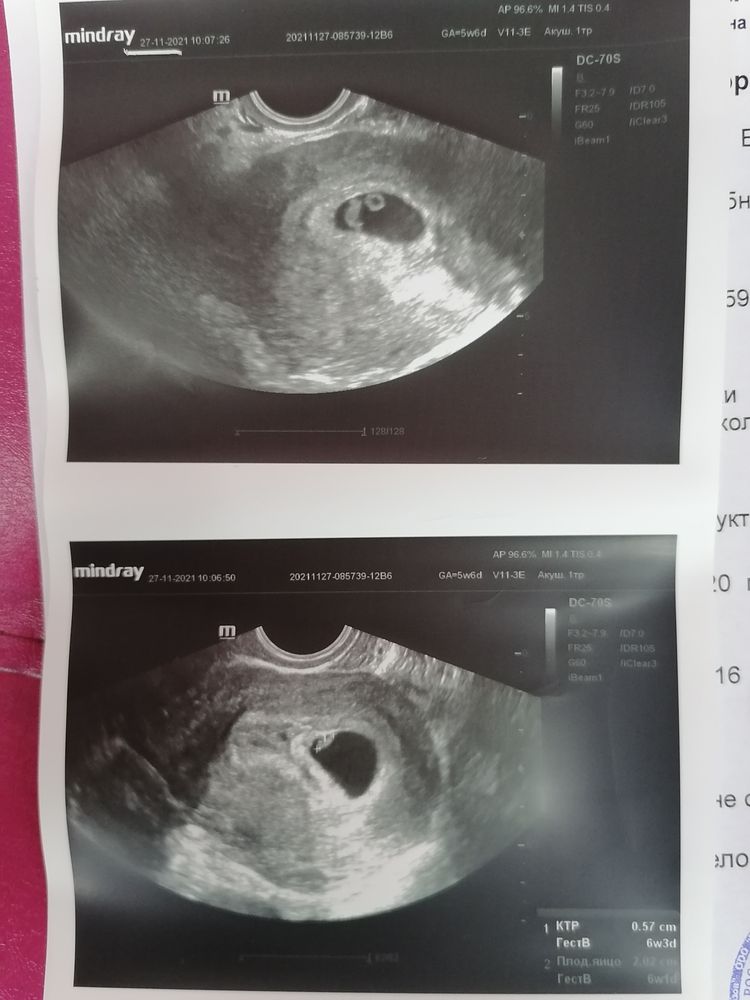

Я ходила с 3 недельной задержкой . Срок поставили по мес 5 недель 6 дней. Был уже эмбриончик и сердечко слышно было Изображение

Ходила на узи вчера, срок был как раз 6н4д по мес. Нашли эмбриончик, определили, что есть чсс, слушать не дали, но показали быстро, так как доплер нагревает ткани. По узи срок поставили 6н2д

Я ходила сегодня на узи. По м 6+5, услышали сердечко. Овуляция, мне кажется, была день на 17й. Но, мне кажется, не обязательно на этом сроке должно быть сб. Честно, думала у меня ничего не услышат и не увидят и отправят гулять недели на 2